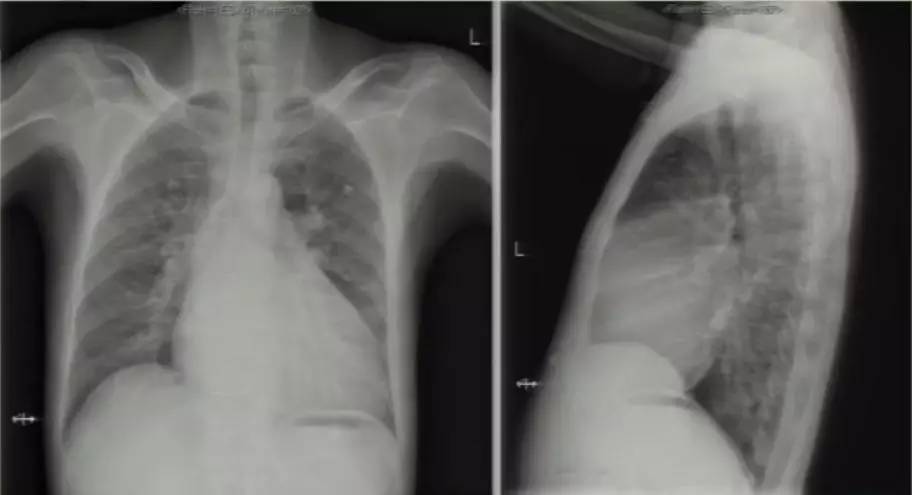

进一步完善相关检查:胸片提示双肺淤血,肺血增多,升主动脉及主动脉结增宽,肺动脉段平直,全心增大,心胸比0.63(图6)。复查超声心动图可见LA 58 mm,LV 53 mm,LVEF 60%,RV 41 mm;房间隔卵圆孔回声分离3 mm,后下部薄弱,探及数处回声脱落,大者约18 mm;二尖瓣前叶发育异常,收缩期瓣体向左房弯曲,致对合不拢。超声提示先天性心脏病(先心病)、Ⅱ孔型房间隔缺损(多发)、卵圆孔未闭、房水平左向右分流 ,二尖瓣脱垂并中大量反流,三尖瓣少中量反流,肺动脉高压49 mmHg。心脏CT提示先心病、房间隔缺损(下腔型),二尖瓣脱垂,双房右室扩大,少量心包积液(图7)。

图6

图7